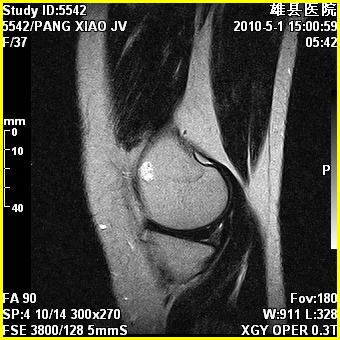

标题: MRI2894:患者右膝关节疼痛两月余,无明显外伤史 [打印本页]

标题: MRI2894:患者右膝关节疼痛两月余,无明显外伤史

右股骨下端前内侧类圆形异常信号,位于干骺端,呈长t1长t2改变,但信号不均,t1图上病灶中心见小片状稍高信号影,t2图上见散在稍低信号影,stir像呈高信号,因病灶较小,缺乏特征性改变,结合患者年龄及部位,考虑嗜酸性肉芽肿可能性大。胫骨关节面下的小囊状异常信号,如果一元论考虑则为嗜酸性肉芽肿,不过发生在这个部位的少见,二元论考虑为邻关节骨囊肿。半月板与前后交叉韧带均未见异常。

内生软骨瘤

年龄略大 内生软骨瘤?

骨样骨瘤?内生软骨瘤?